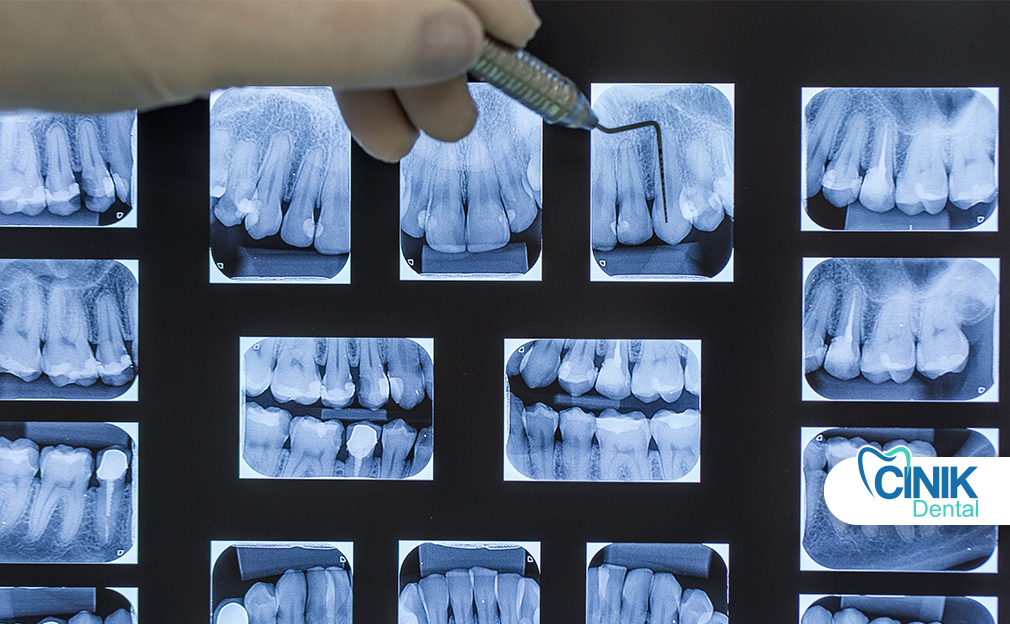

Panoramic dental X-rays provide a single, wide-view image of the entire mouth, including teeth, jaws, and surrounding bone structures. They are commonly used in orthodontics, oral surgery, and complex diagnostic cases to assess tooth position, jaw anatomy, wisdom teeth, and hidden pathologies such as cysts or tumors. The procedure is quick, painless, noninvasive, and uses a relatively low radiation dose compared to traditional X-rays.

Panoramic dental X-rays display the entire jaw in a single image and are employed to determine the position of teeth, bone structure, and potential abnormalities. Dentists take panoramic X-rays for several reasons. First, they allow assessment of bone anatomy and pathology, dental development, and the extent of dental treatment. Second, they evaluate the mandible and maxillofacial region for certain lesions, cysts, and tumours not visible through intraoral films. Third, they detect gross caries, periodontal disease, or other pathology overlooked on intraoral films. Lastly, they are valuable for identifying unerupted teeth, especially wisdom teeth, and establishing their relationship to adjacent teeth (Ozmen and Basak Ayna, 2024).

Panoramic radiographs are a simple and widely used technique in dental specialties that involve synchronized rotation of an X-ray source and a stationary image receptor around the patient's head. This imaging method captures the entire maxillomandibular structure, including dental arches and related structures. It is beneficial because it involves a lower radiation dose, costs less, and images a larger area compared to intraoral radiographs. Panoramic radiography is recommended for patients with transitional or permanent dentition and can evaluate teeth, bone lesions, fractures, and foreign bodies (Couto Ramos et al., 2016).

Dental X-ray surveys help dentists make decisions about patients’ oral health, treatments, and hygiene. Panoramic X-rays or panoramic, generically exposed images allow a single depiction of the maxillary complex. They help outline the dentition contour, bone structure, and teeth alignment in both the upper and lower jaw (眞之, 2018). These X-rays expose the patient to significantly lower radiation levels than conventional periapical X-ray techniques.